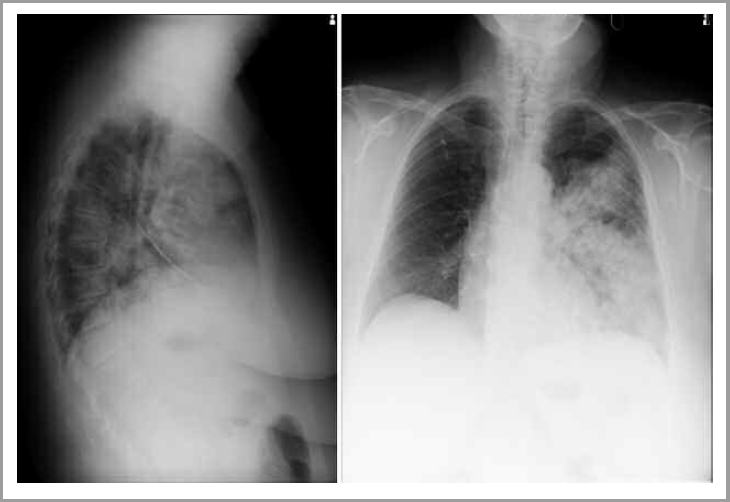

По данным ЭКГ – синусовая тахикардия до 140 уд/мин, депрессия сегмента ST в III, avF, отведениях V5–V6. На рентгенограммах органов грудной полости в двух проекциях (левая боковая) субтотально понижена воздушность левого легочного поля за счет фокусов массивной инфильтрации сливного характера без четких контуров в проекции S3, S6, S8–10, язычковых сегментов с реакцией косой междолевой плевры в виде ее утолщения, неоднородной структуры за счет участков просветления (рис. 1).

Рис. 1. Рентгенограмма органов грудной клетки в прямой и боковой проекции.